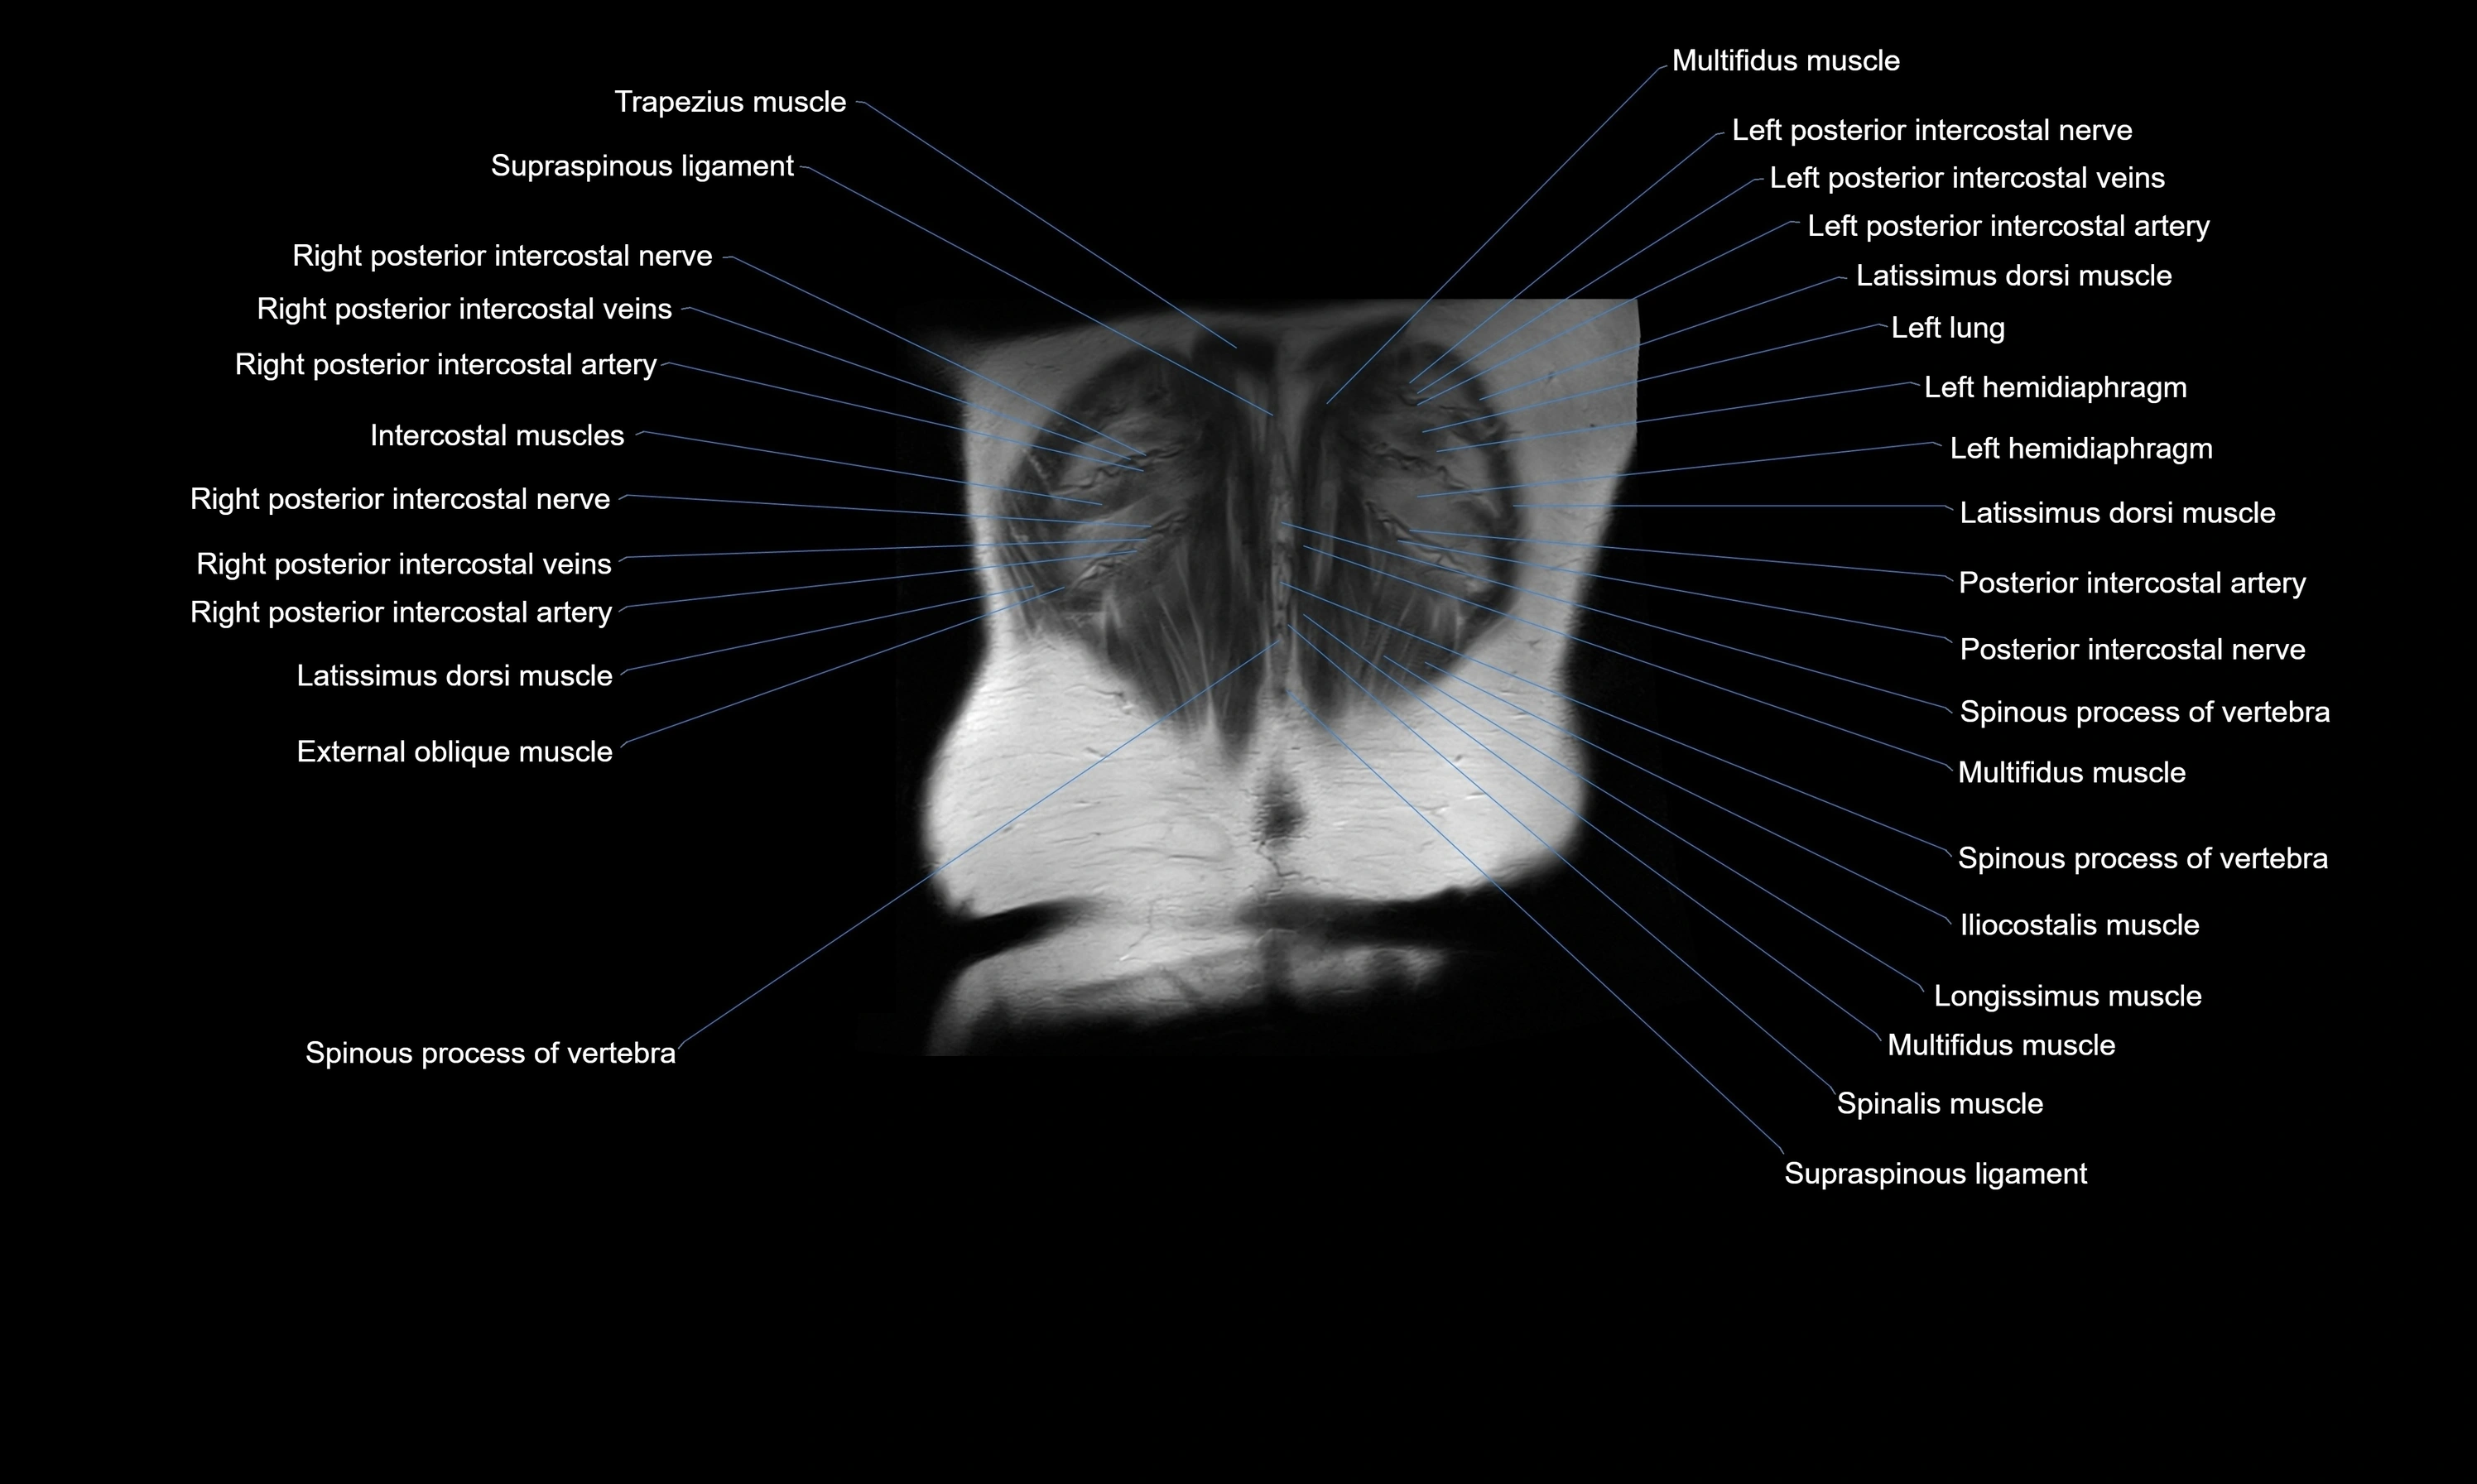

- Intercostal muscles

- Latissimus dorsi muscle

- Longissimus thoracis muscle

- Spinous process of vertebra

- Supraspinous ligament